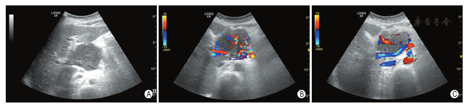

患者女,73岁,汉族,因左上腹疼痛1月余入院,自发病以来精神、食欲一般,大小便正常,体重减轻约3 kg。行超声内镜下胰腺穿刺活检术,病理示:送检组织太少无法明确。查体:左上腹部有深压痛,无反跳痛,腹部末触及包块,肝脾未触及,Murphy征(-)。实验室检查:肿瘤标记物正常,脂肪酶429.5 IU/L,胰淀粉酶110 U/L。超声检查:见右上腹一大小6.8 cm×5.1 cm的低回声区,形态欠规则,边界尚清,内回声不均,与胰腺分界不清。彩色多普勒血流显像(CDFI):上述低回声区内可见丰富血流信号。超声提示:右上腹实质性病变(考虑肿瘤性病变,来源于胰腺可能)。增强CT见胰头软组织肿块,大小约69 mm×65 mm×59mm,包绕腹腔干及分支,肝总动脉局部管腔变窄,门脉主干与病灶关系密切。肿块轻度强化,胰体尾部胰管稍扩张,胰尾周围间隙模糊。CT提示:胰头肿瘤,考虑淋巴瘤可能,神经内分泌肿瘤不除外。增强CT与超声均未能明确肿瘤性质,鉴别原发性胰腺淋巴瘤与胰腺癌,可排除临床所怀疑的梗阻性黄疸。故经皮胰腺穿刺活检术后,病理诊断:(胰腺)非霍奇金B细胞淋巴瘤(侵袭性),考虑为弥漫性大B细胞淋巴瘤。免疫组化:CD20、CD19、PAX-5、BCL-2、CD43(+);BCL-6、HGAL、CD21、LEF1、Mum-1、Vim、P53(部分+);C-myc(少许+);CD3、CD5、CyclinD1、SOX11、IgD、CD23、CD10(LN)、CD30(-);PCK、CK8/18、CK7(-);Ki-67(LI约80%);EBER CISH(-)。病理回报后建议从胆胰外科转肿瘤科化疗,患者及家属拒绝转科,转回当地医院治疗。经随访:患者回当地医院治疗,经4期CHOP方案化疗和放射治疗,患者肿瘤有所缩小。

PPL的CT检查常表现为胰腺实质内软组织肿块,体积较大时肿块内部密度不均,伴腹膜后多发淋巴结肿大,肿大淋巴结推移、包绕邻近血管,可出现"腹主动脉淹没征"或"血管脂肪角"消失[4]。由于其影像学表现特异性不高,容易误诊。除伴发胆管梗阻外,PPL患者血清CA19-9、CA125、CEA多在正常范围,而80%的胰腺导管腺癌CA19-9水平升高[5]。白新华等[6]对胰腺淋巴瘤和胰腺癌超声特点进行了比较,发现两者在病灶部位、内部回声及血供方面无显著性差异,而在病灶大小、胆管、胰管扩张及腹膜后淋巴结肿大方面有显著性差异,胰腺淋巴瘤肿块体积更大,伴胆管、胰管扩张少,多伴腹膜后淋巴结肿大[6]。对超声医师而言,胰腺肿块若有以下表现应考虑PPL的可能:①肿瘤较大(>6 cm),胰管不扩张或轻度狭窄;②肿瘤呈浸润性生长;③包绕大血管;④通常不表现为钙化及坏死;⑤通常不累及肝、脾[7]。